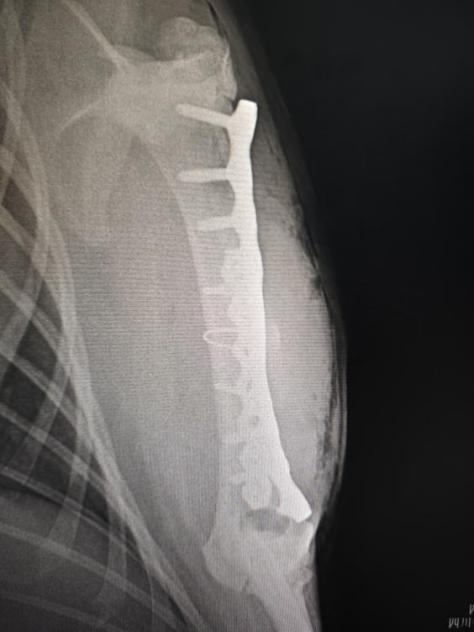

手术后左前肢腹背位X光

手术团队由必赢中国官方网站教学动物医院院长沈留红、动物外科专家石先鹏、动物内科专家巫晓峰、医生陈善瑜和罗皓、麻醉医生邓聪辉、手术助手王郡东、助理唐清婷、张涵艺、钱琳、王均、李鑫等组成,并与动物园动物疾病预防组刘俊卿副经理团队一道组成会诊专家组,确定麻醉和手术方案。外科专家石先鹏凭借丰富的经验和精湛的技术,对水豚肱骨进行了精确的复位和固定。手术全程在严格的无菌条件下进行,确保了安全性和成功率。